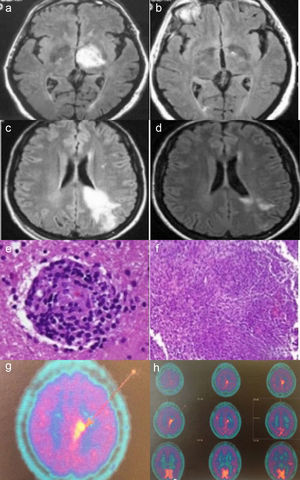

Caso 1: RMN axial FLAIR mostrando lesión hiperintensa en tálamo izquierdo (a). Dos meses después con resolución completa de la lesión (b).

Caso 2: RMN axial FLAIR mostrando una lesión hiperintensa en la sustancia blanca izquierda del área frontoparietal extendiéndose hasta córtex y cuerpo calloso con realce tras gadolinio (c). Después de veinte días de corticoterapia una nueva RMN mostró una importante reducción del componente hiperintenso (d). Hallazgos histopatológicos de la biopsia cerebral que muestran un infiltrado linfocítico perivascular con afectación de los vasos sanguíneos (hematoxilina-eosina) (e). Infiltrado inflamatorio granulomatoso (hematoxilina-eosina), (f). Imagen de PET cerebral con metionina, que evidencia depósito parasagital de C11-metionina sugerente de posible linfoma (g y h).

Casos clínicosCaso1Varón de 63 años, que consultó por alteración de conducta en forma de irritabilidad, agresividad y labilidad emocional, así como dificultad para la marcha y agrafia de un mes de evolución. En la anamnesis el paciente refería historia de úlceras orales recurrentes de 35 años de evolución y genitales en los últimos 6 meses, acompañadas de foliculitis en región genital y extremidades inferiores. En la exploración física se constató desorientación temporoespacial, bradipsiquia, paresia faciobraquiocrural derecha 4/5 y marcha lateralizada a la derecha, junto a úlceras orales y genitales. En las pruebas de laboratorio destacaban: reactantes de fase aguda elevados, serologías para Brucella, sífilis, VHB, VHC, VIH negativas, y estudio de autoinmunidad negativo. Se cursó HLA B51 que resultó positivo. La resonancia magnética nuclear (RMN) cerebral evidencio una lesión ocupante de espacio en el tálamo izquierdo (fig. 1.1). La angiografía de troncos supraaórticos evidenció angioesclerosis de pequeño vaso y afectación ateromatosa de las bifurcaciones carotídeas, así como aneurismas saculares e infundibulares con imágenes de ovillos vasculares en el territorio carotídeo izquierdo, sugestivos de vasculitis. La tomografía toracoabdominal resultó normal. La punción lumbar dio salida a un líquido cefalorraquídeo cristalino con discreta proteinorraquia, sin presencia de bandas oligoclonales. Ante sospecha de NB, se iniciaron pulsos de metilprednisolona seguidas de prednisona oral (1mg/kg/día), colchicina 1mg/12h y azatioprina oral (2mg/kg/día). El paciente presentó mejoría clínica, con desaparición de las úlceras genitales y recuperando su déficit neurológico. Tras 3 meses de tratamiento, se realizó RMN cerebral de control que evidenció una completa resolución de la lesión (fig. 1.2). Tras 15 años de seguimiento, el paciente se encuentra asintomático de la clínica neurológica, sin tratamiento alguno, no obstante ha presentado de forma esporádica aftas bucales que mejoraron con colchicina.

Mujer de 35 años que consultó por crisis convulsiva generalizada. Refería clínica de parestesias en región malar derecha de dos meses de evolución. La exploración física fue normal. En la analítica destacó: elevación de reactantes de fase aguda, serologías virales para VIH, VHB, VHC negativas, y estudio de autoinmunidad negativo. La RMN craneal evidenció una lesión infiltrativa intraparenquimatosa que afectaba al área frontoparietal izquierda con realce de la captación tras la administración de gadolinio (fig. 1.3), que fue informada como tumor cerebral. Se practicó una punción lumbar: líquido claro acelular, con discreta hiperproteinorraquia, sin presencia de bandas oligoclonales. Se inició tratamiento con dexametasona (12mg/día/IV) con posterior pauta descendente. Tras 20 días la RMN cerebral evidenciaba una reducción significativa de la lesión (fig. 1.4). Se realizó un PET cerebral con metionina, que sugirió linfoma cerebral (figs. 1.7 y 1.8). Se realizó biopsia de la masa cerebral. El estudio histológico evidenció un infiltrado granulomatoso focalmente necrosante con vasculitis linfocitaria (figs. 1.5 y 1.6). Las tinciones de Ziehl-Neelsen, PAS y plata, fueron negativas. Se realizó una TC toracoabdominal, gammagrafía con galio 67, y biopsia transbronquial, que descartaron sarcoidosis. Tres meses después, se evidenciaron úlceras orales y genitales. Se cursó HLA B51 que resultó positivo. Se orientó como NB y se inició tratamiento con pulsos mensuales de ciclofosfamida 1g/mes más dosis descendentes de glucocorticoides. Cinco meses después presentó un nuevo episodio de crisis comicial, se realizó una nueva RMN craneal que evidenció un aumento del tamaño de la lesión. Se suspendió ciclofosfamida por ineficacia, iniciándose tratamiento con azatioprina oral (2mg/kg/día) y se aumentó la dosis de prednisona a 30mg/día, con posterior pauta descendente. A los 4 meses, la RMN craneal no evidenció mejoría de la lesión, por lo que se decidió iniciar tratamiento con infliximab (3mg/kg/iv. cada 8 semanas). Tras 8 dosis de infliximab la masa cerebral disminuyó significativamente; pero la paciente experimentó artralgias difusas rechazando dicho tratamiento, que se sustituyó por adalimumab con buena tolerancia. En la actualidad 5 años después, se mantiene tratamiento con adalimumab 40mg/15 días subcutáneo, en monoterapia con buena tolerancia y sin progresión de su lesión cerebral, durante su evolución presentó episodios de úlceras bucales que se resolvieron con tratamiento sintomático.